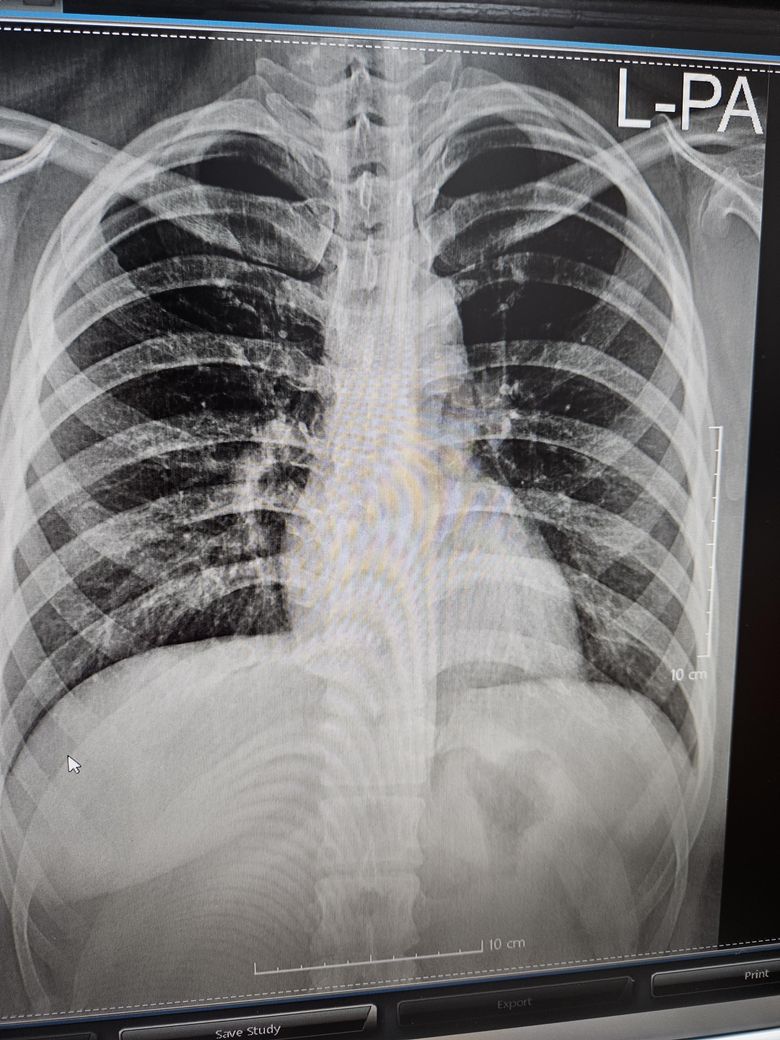

Chest pa 사진입니다. 병원에 가봐야하나요? 아니면 그냥 정상인지요?

건강검진한다고, xray 촬영을했는데

xray상 조금 하얗게 보이는거같아서

(코로나3번걸렸습니다.)

X-ray 화질이 좋지않아서 좀 애매하지만,, 우측폐에서 좀 지저분하게 보이기는 하네요. 코로나 이후에 염증소견으로 저렇게 보일수도 있긴 할거 같습니다. 증상 없다면 1달쯤 후에 X-ray 다시 찍어볼수도 있고,, 확실하게 검사하고 싶다면 흉부 CT 고려해볼수 있을거 같습니다.